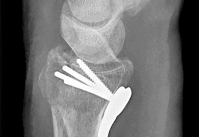

Question 6:

During a primary posterior-stabilized total knee arthroplasty, the surgeon assesses the flexion and extension gaps. The knee is found to be tight in both extension and flexion. Which of the following surgical adjustments is the most appropriate next step?

Correct Answer: Resect more proximal tibia

Explanation:

In gap balancing for total knee arthroplasty, the proximal tibial cut affects both the flexion and extension gaps equally. If the knee is symmetrically tight in both flexion and extension, resecting more proximal tibia (or using a thinner tibial polyethylene insert) will increase both gaps equally. Resecting more distal femur would only loosen the extension gap. Changing the femoral size primarily affects the flexion gap (downsizing loosens flexion; upsizing tightens flexion).